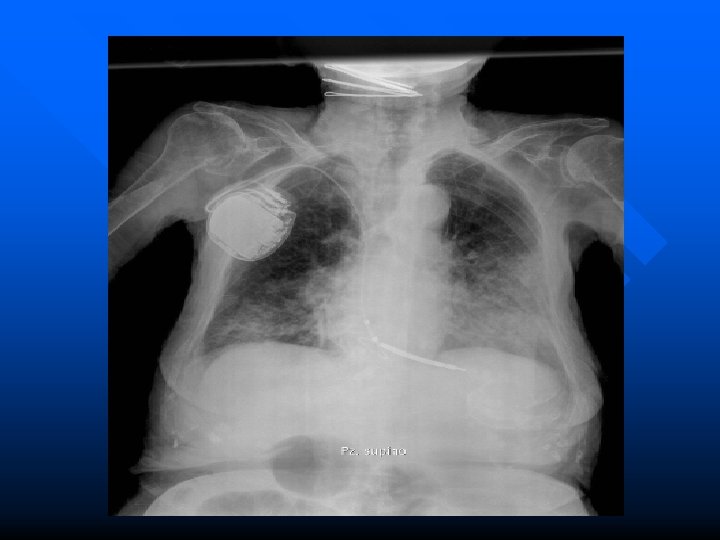

DIAGNOSI clinicamente è possibile sulla base di una sintomatologia bronchitica ricorrente che non trovi spiegazione. Dal punto di vista strumentale, rmai in disuso le vecchie metodiche radiologiche broncografiche, oggi la diagnosi di bronchiectasie è possibile ed agevole attraverso un semplice esame TAC del torace ad alta definizione senza mezzo di contrasto (HRCT-Torace). Esami complementari, quali gli esami colturali batteriologici sull’espettorato per la ricerca di germi residenti anche pericolosi e le prove di funzionalità respiratoria sono utili strumenti per orientare correttamente la prevenzione degli episodi infettivi e la terapia.